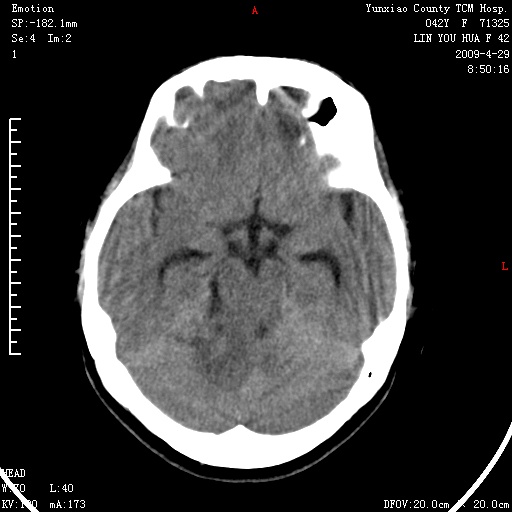

右侧桥小脑角区肿瘤,高密度囊变有显著强化,骨窗见内听道显著扩大,考虑听神经瘤可能性大

1)右侧听神经瘤。2)阻塞性脑积水。

内听道扩大,支持考虑听神经瘤可能性大。